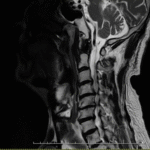

重度の頚椎ヘルニアの症例

重度の頚椎ヘルニア・肩から指までの痛みと痺れの症例 【大阪市 70代男性】 30年間接骨院に通院していましたが、頭痛と肩こりに加え腕の痛みと痺れが取れず、最近は腕も細くなってきたので整形外科へ。MRI…